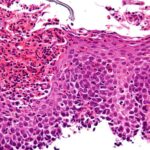

Das nicht-kleinzellige Lungenkarzinom über alle Stadien im Blick